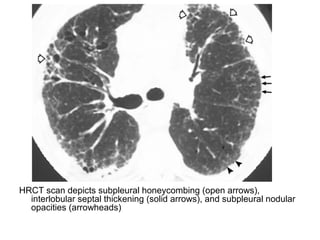

HRCT scan depicts subpleural honeycombing (open arrows),

interlobular septal thickening (solid arrows), and subpleural nodular

opacities (arrowheads)